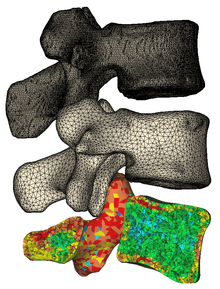

3D surface models created in Mimics from CT | |

Process

Materialise Mimics calculates surface 3D models from stacked image data such as Computed Tomography (CT), Micro CT, Magnetic Resonance Imaging (MRI), Confocal Microscopy, X-ray and Ultrasound, through image segmentation. The ROI, selected in the segmentation process is converted to a 3D surface model using an adapted marching cubes algorithm that takes the partial volume effect into account, leading to very accurate 3D models.[2][3] The 3D files are represented in the STL format.

Output file formats differ, depending on the subsequent application: common 3D output formats include STL, VRML, PLY and DXF. The 3D files can also be optimized for FEA or CFD and can therefore be exported to Abaqus in INP format, to Ansys in INP, CDB and MSH format, to Nastran in OUT, NAS and BDF format, and to Comsol in MPHTXT format. To continue with Computer-aided design, the files can be exported in IGES format or as Point cloud.

- Finite Element Analysis: ABAQUS, ANSYS,...etc.